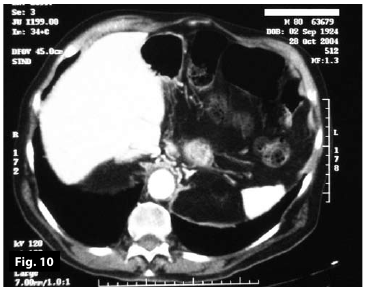

Figure7-8

Figure5-6-7-8